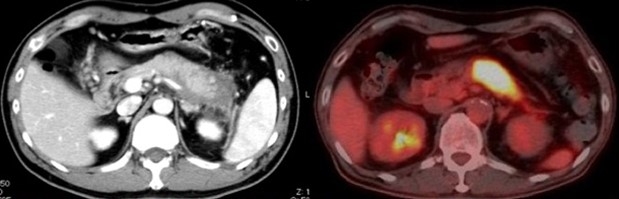

自己免疫性膵炎は高齢男性によく発症する指定難病で、膵臓が大きく腫れて黄疸・腹痛を伴い、悪化と治癒を繰り返すことが特徴です。この自己免疫性膵炎は、IgG4という特殊な抗体を作る免疫細胞が膵臓に集まることで発症するIgG4関連疾患であることが知られています。

まず、マウスにpoly(I:C)※8を反復投与し、自己免疫性膵炎モデルマウスを作成しました。モデルマウスを用いて検証を行った結果、発症初期には膵臓に炎症の原因とされる形質細胞様樹状細胞はほとんど存在せず、活性化された通常型樹状細胞がサイトカインであるI型IFNとケモカインであるCXCL9・CXCL10※9を産生し、初期の炎症を誘導することが明らかになりました。次に、CXCL9・CXCL10に反応してCXCR3陽性CD4T細胞が膵臓に誘導され、この細胞がさらなる炎症をもたらすことがわかりました。また、CXCR3陽性CD4T細胞はインターフェロン-γ※10を産生し、膵臓にダメージを与える一方で、ケモカインCCL25※11を膵臓で産生します。このCCL25が、最も炎症に大きな影響を与える形質細胞様樹状細胞を最終的に膵臓に引き寄せ、炎症が完成することが明らかになりました。つまり、通常型樹状細胞とCXCR3陽性CD4T細胞が初期の炎症を誘導し、CXCR3陽性CD4T細胞と形質細胞用樹状細胞が炎症を完成させることがわかりました(図)。さらに、完成期には形質細胞様樹状細胞とCXCR3陽性CD4T細胞が相互に活性化しあい、大量のI型IFN・CXCL9・CXCL10・CCL25が放出され、炎症が加速することも突き止めました。また、実際にTLR3・CXCR3・CCL25・I型IFNを阻害すると、炎症はほとんど起こりませんでした。ここから、通常型樹状細胞・形質細胞様樹状細胞・CXCR3陽性CD4T細胞を自己免疫性膵炎・IgG4関連疾患の病的細胞と同定し、病気の初期・完成期におけるこれらの細胞の役割をサイトカイン・ケモカインのレベルで明確にすることができました。

最後に、自己免疫性膵炎・IgG4関連疾患患者の血液を用いた検討を行いました。その結果、活動期の自己免疫性膵炎・IgG4関連疾患では、血液中のI型IFN・CXCL9・CXCL10・CCL25が、健常人・慢性膵炎患者と比較して著明に上昇することがわかりました。また、ステロイドにより病気が改善すると、血液中のI型IFN・CXCL9・CXCL10・CCL25は著明に低下しました。